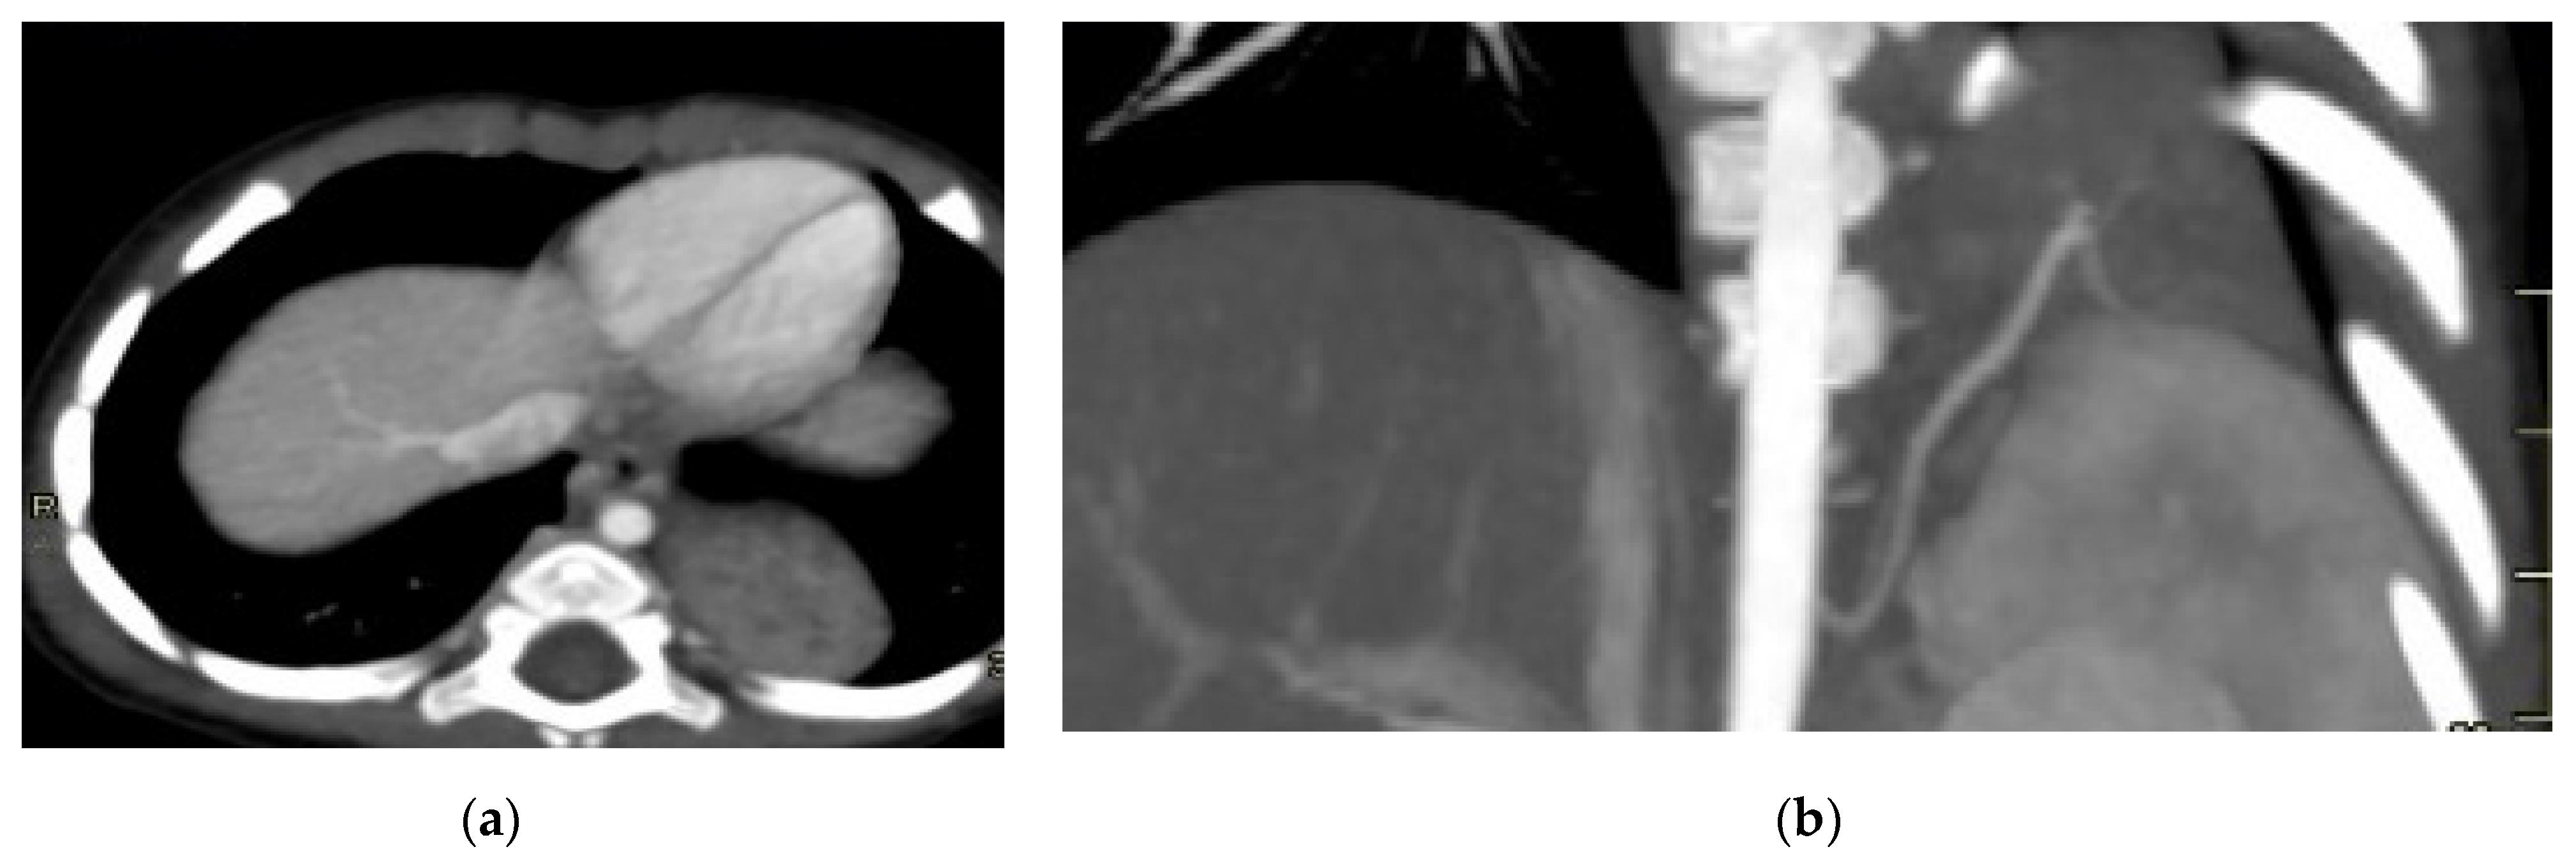

Figure 8. Intra-lobar bronchopulmonary sequestration. The Contrast-enhanced computed tomography (CECT) axial (a), coronal MPR reconstruction (b), and volume rendering reconstruction (c) images show a parenchymal consolidation located in the lower left lobe supplied by an afferent artery originating from the suprarenal tract of the abdominal aorta. Intraoperative findings confirmed the bronchopulmonary sequestration (d).

Intra-lobar sequestration, on the other hand, is typically located within the normal lung parenchyma, often in the posterobasal segment of the left lower lobe. It is characterized by an anomalous artery arising from the abdominal aorta and a vein draining into the pulmonary venous system [11]. The CT appearance of sequestration can range from a homogeneous soft tissue mass to a cystic lesion containing air or fluid, with hybrid forms also possible.

For postnatal evaluation, CT and CT angiography are the methods of choice, as they provide clear visualization of vascularized parenchymal consolidation with arterial supply from the descending or abdominal aorta (Figure 8).